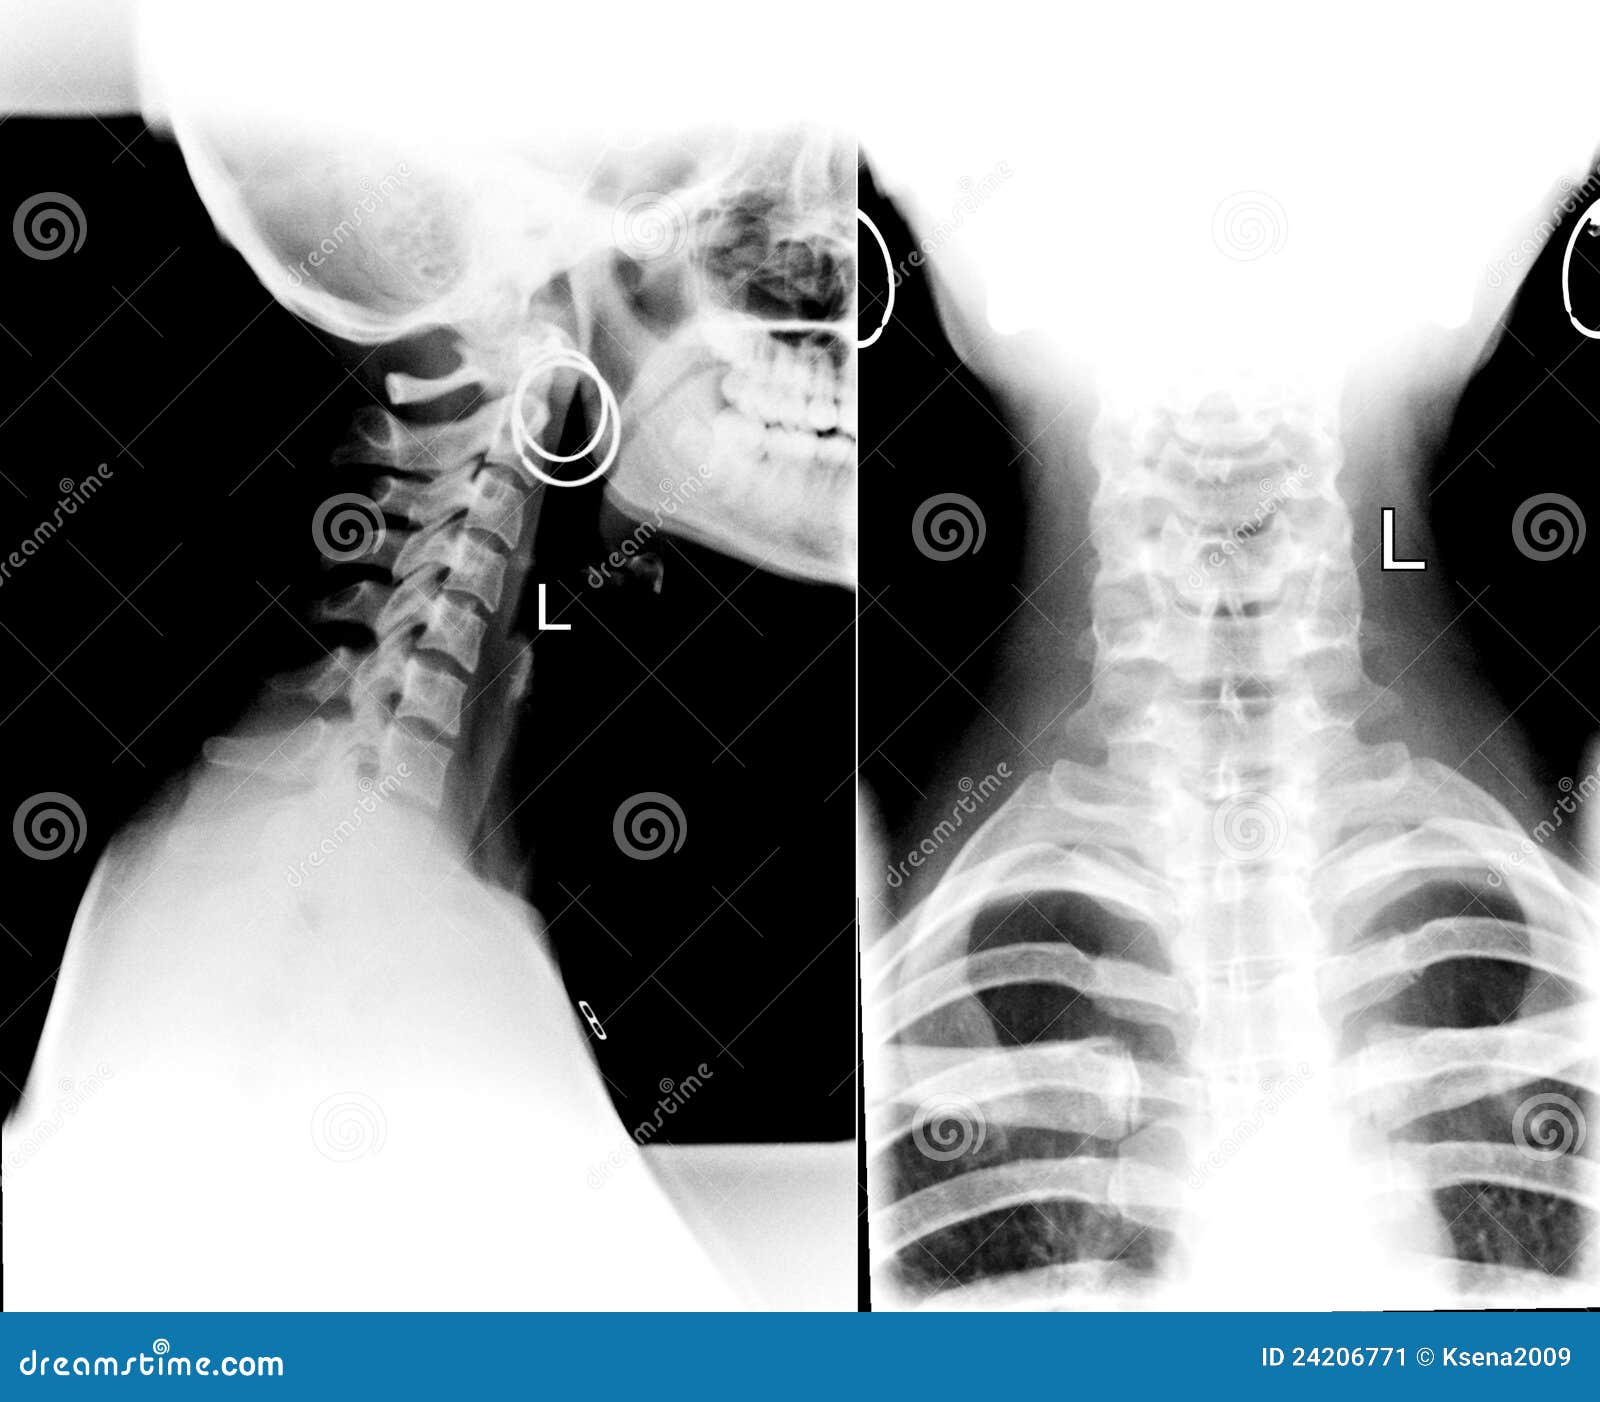

Detail Of Neck Xray Stock Image Image 24206771 Why Is My Neck X Ray Straight Normally the cervical spine (neck). straight neck syndrome or loss of neck curve is a widespread condition nowadays. This is the natural inward curvature of the neck that helps support the head and maintain proper alignment of the spine. straight neck syndrome, also known as military neck, is a condition characterized by the loss of normal cervical lordosis.. Why Is My Neck X Ray Straight.